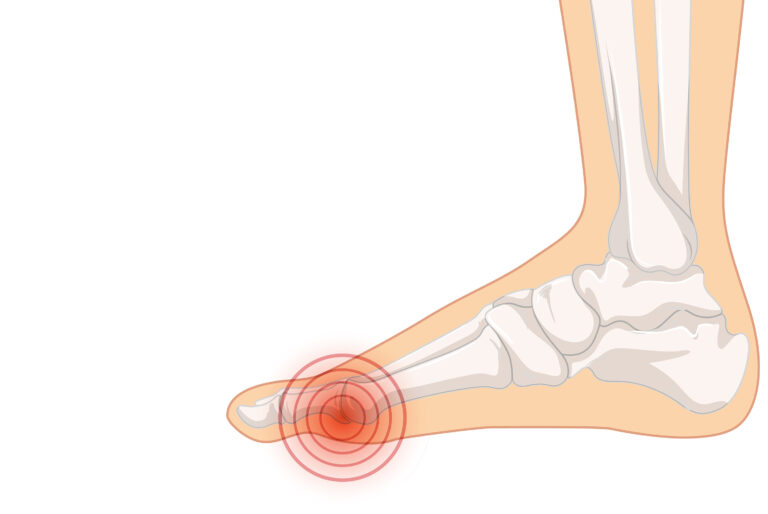

La metatarsalgia: cos’è, come si riconosce e come si cura

La metatarsalgia è un’infiammazione delle articolazioni metatarso-falangee, ovvero le articolazioni che collegano le ossa lunghe del piede (i metatarsi) alle dita. Questa infiammazione è causata da un sovraccarico funzionale delle articolazioni, che provoca dolore, gonfiore